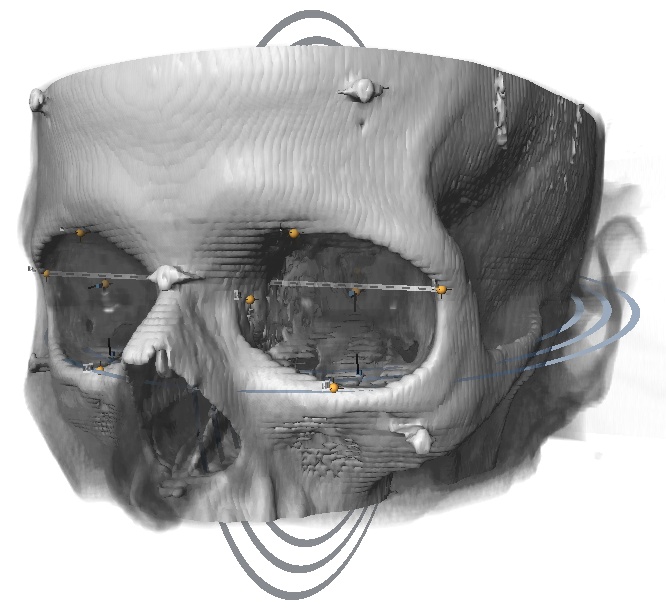

Stratovan Maxillo™ computes orbit (eye socket) volumes and bony contour shapes directly from x-ray computed tomography (CT) image data. Maxillo is intended for research use only by otolaryngologists, ENTs, plastic, and maxillofacial researchers investigating orbit morphology, shape, volume, and globe position. Maxillo utilizes a patent-pending image segmentation method.